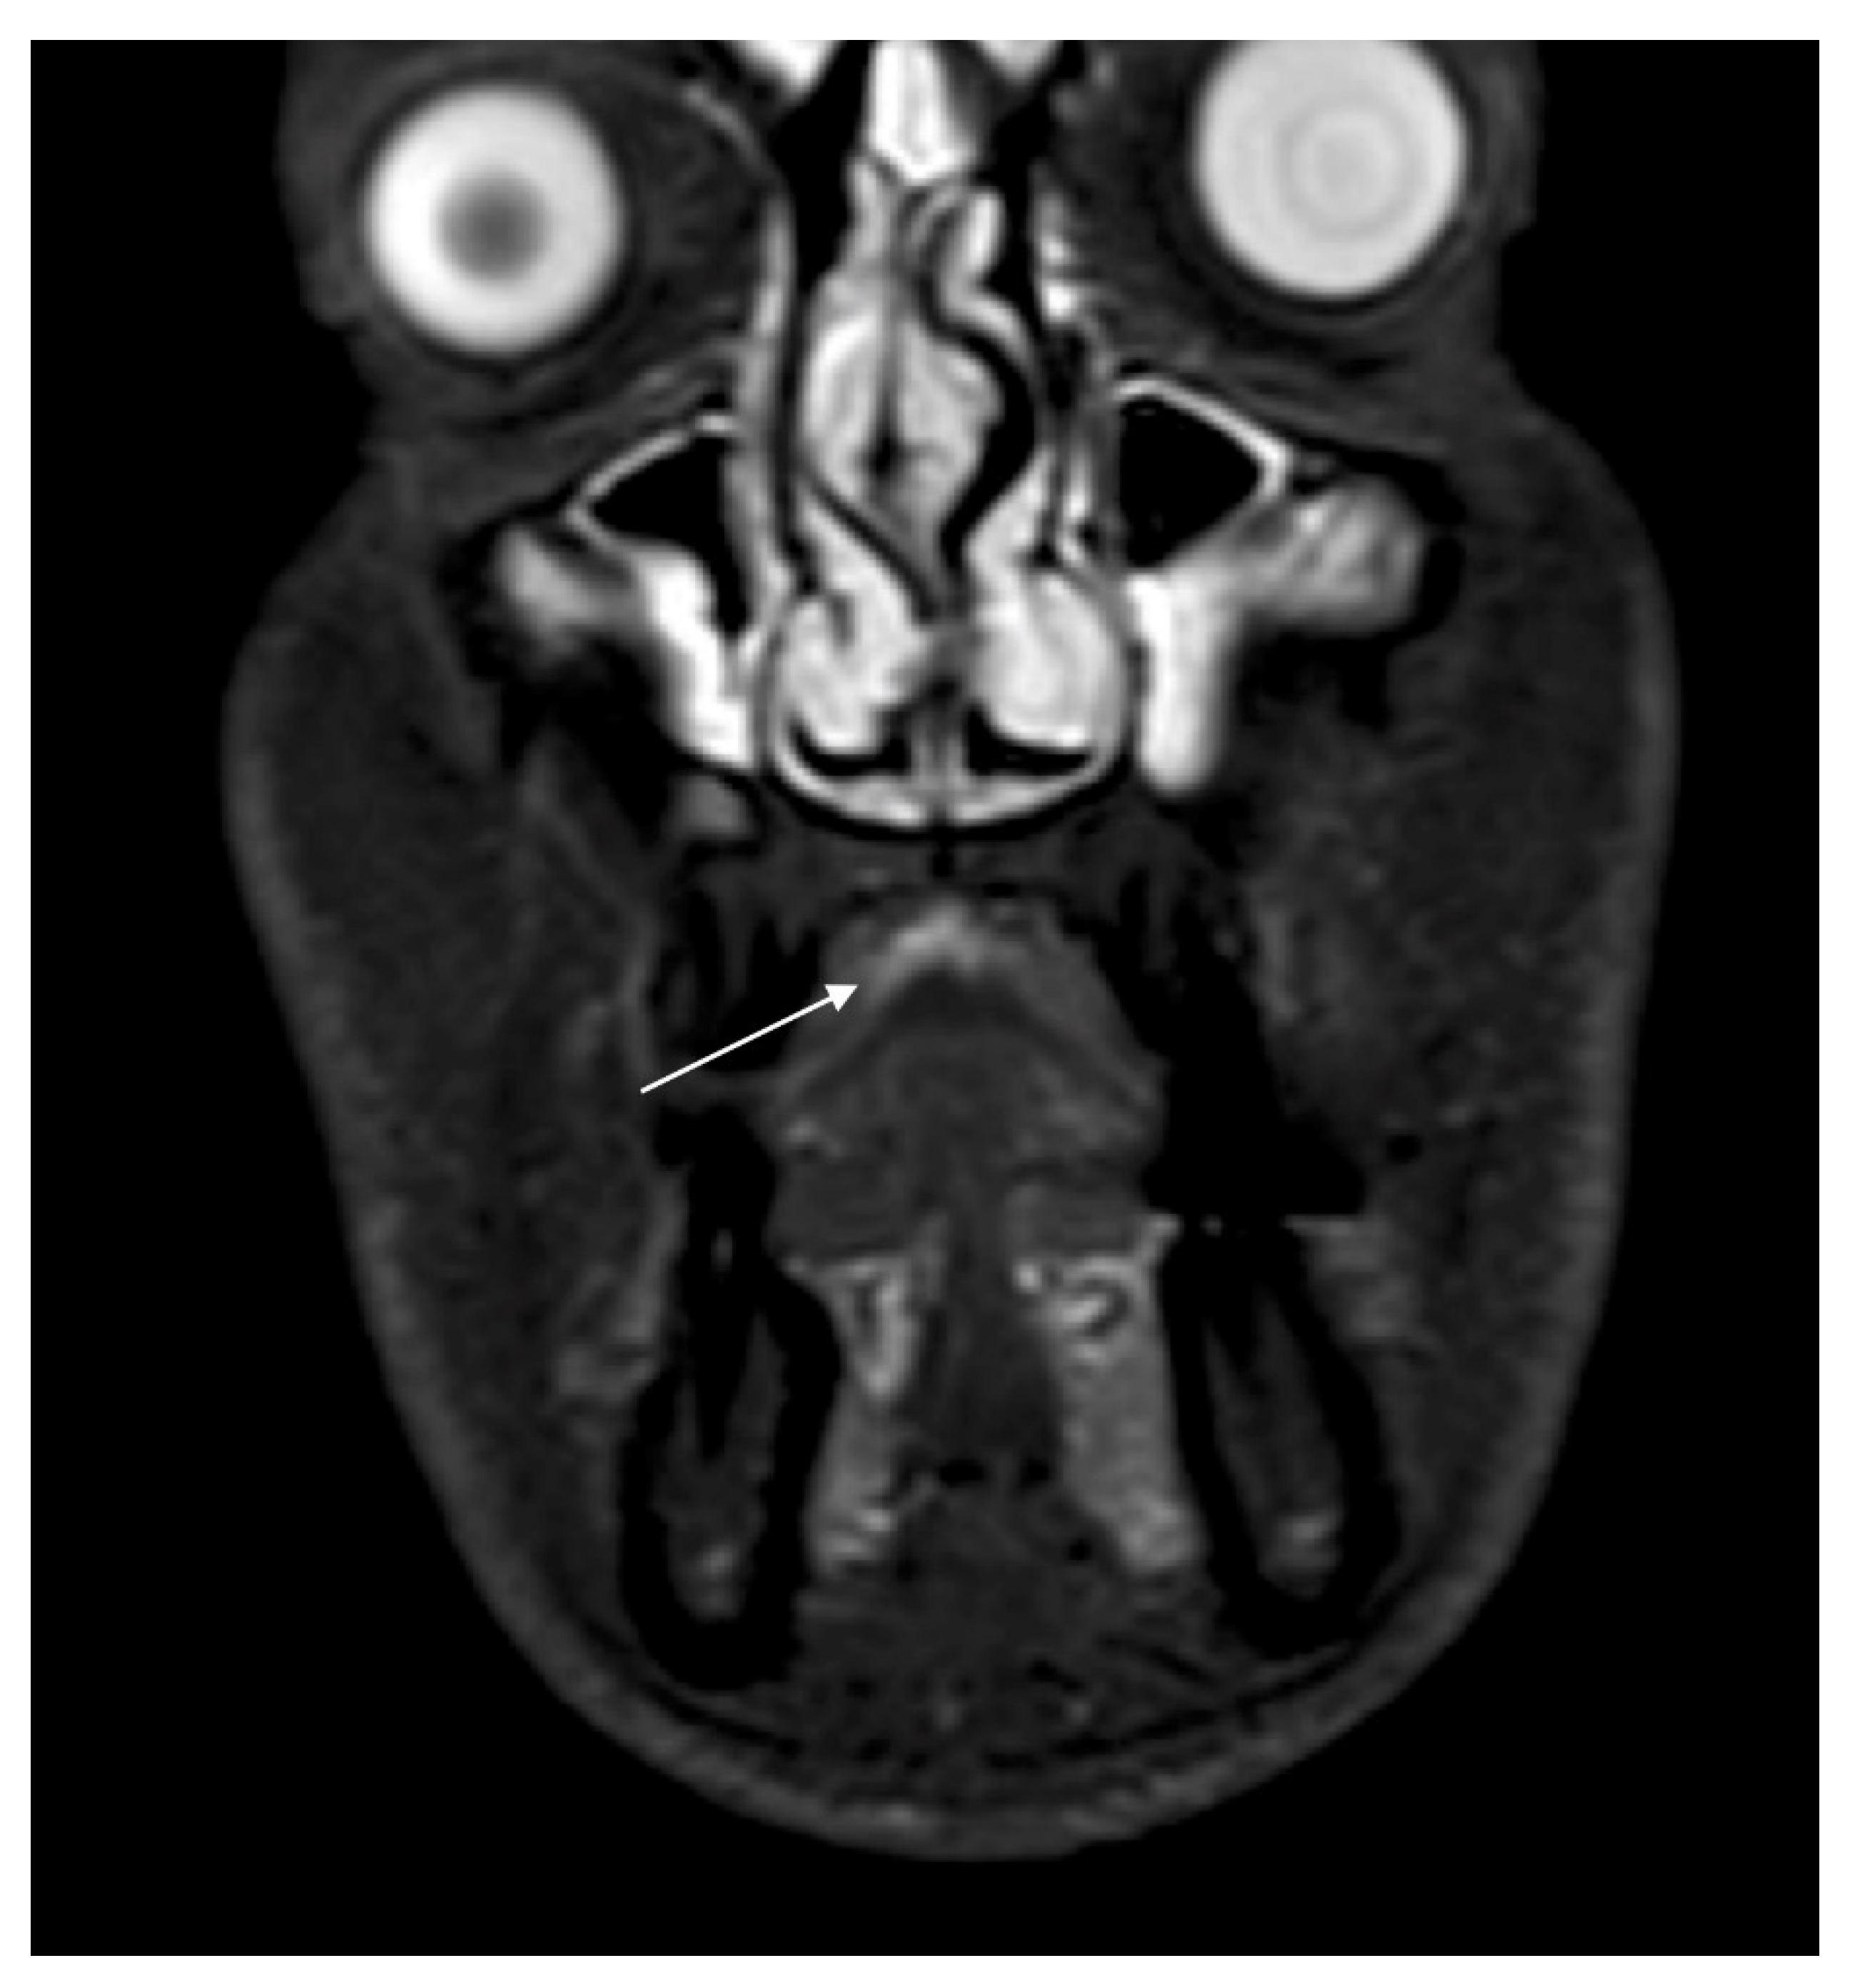

2. Case Report